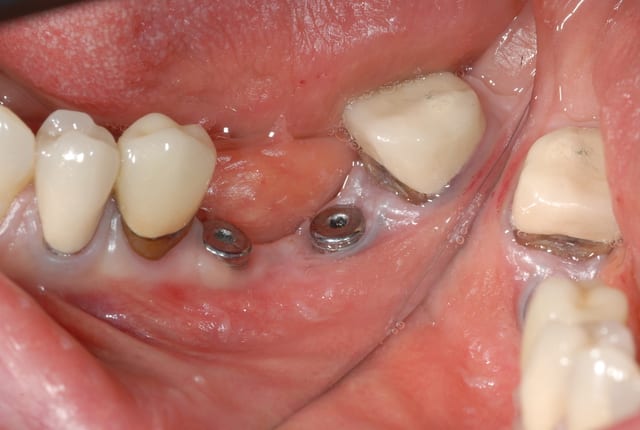

Bonjour à tous

je souhaiterai gagner de la gencive attachée en vestibulaire de 46 et 45 avant la pose des dents.

Dans le cas présenté, j avais fait extraction implantation de la 46 et pose de l implant en 45, la gencive n était pas terrible déjà, j ai gagné du conjonctif en 45 grâce à mon trace d incision mais pas en 46.

Je préfère pour cette raison, même après la pose des implants, améliorer le site et avoir un bandeau de gencive attachée avant de poser les dents.